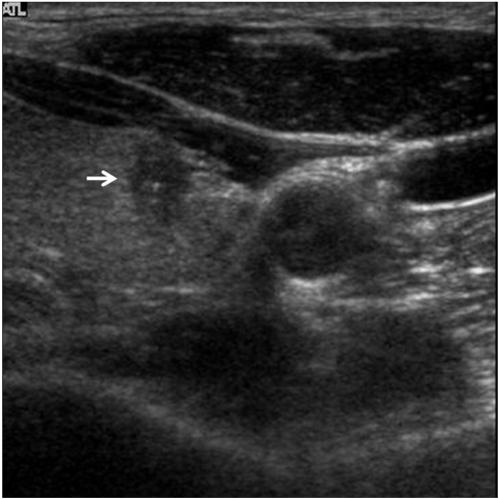

The common US findings for MTCs were solid internal content (91%), an ovoid to round shape (57%), marked hypoechogenicity (52%) and calcifications (52%). Among the 21 cases of MTC nodules, 17 (81%) were classified as suspicious malignant nodules. The mean size (longest diameter) of MTC nodules was 19 +/- 13.9 mm and the mean size (longest diameter) of PTC nodules was 11 +/- 7.4 mm; this difference was statistically significant (p < 0.05). An ovoid to round shape was more prevalent for MTC lesions than for PTC lesions (p < 0.05).

MTC常见的US表现为内部实性成分(91%)、卵圆形至圆形(57%)、明显低回声(52%)和钙化(52%)。在21例MTC结节中,17例(81%)被分类为可疑恶性结节。MTC结节的平均大小(最长直径)为19±13.9mm,PTC结节的平均大小(最长直径)为11±7.4mm;这种差异具有统计学意义(p<0.05)。MTC病变中卵圆形至圆形比PTC病变更常见(p<0.05)。